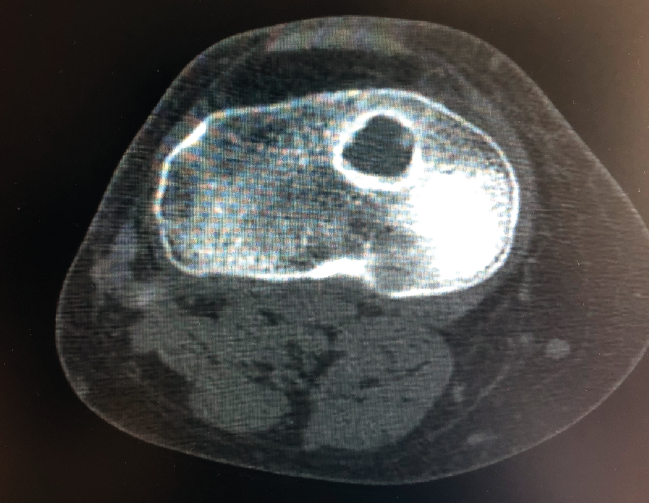

Un diagnóstico y una planificación correctos son fundamentales. En caso de rotura de plastia del LCA (Figura 3), se hace obligatoria, además de una detallada exploración, un correcto estudio radiológico completo que incluya radiología convencional y resonancia magnética (RM) –estudio de lesiones acompañantes o degeneración previa–. En ocasiones en donde la anamnesis/exploración lo justifique, pueden ser también necesarias telemetrías de extremidades inferiores, radiología forzadas (si existiera inestabilidad mediolateral) o tomografía axial computarizada (TAC) –valoración de la posición y la calidad de los túneles–.

Figura 3. Rotura de la plastia del ligamento cruzado anterior.